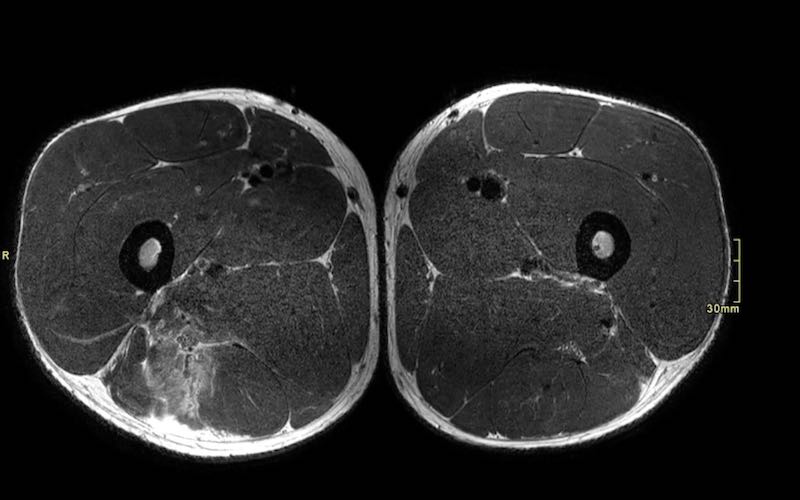

Trên các hình ảnh axial này, có thể thấy tăng tín hiệu và dày lên của gân cơ nhị đầu đùi bên trái (vòng tròn chấm vàng) khi so sánh với bên không bị tổn thương (vòng tròn chấm trắng).

Tại đây bạn có thể cuộn qua các hình ảnh axial. Có thể phóng to hình ảnh bằng cách nhấp vào chúng.

Đây là tổn thương bán phần, bắt đầu từ gân chung ở phía gần, bao gồm cả vùng MTJ và gân trong cơ ở phía xa hơn. Chiều dài vùng phù nề và mức độ biến dạng gân đều ở mức độ cao. Trường hợp này được phân loại là tổn thương BAMIC 3b/c.